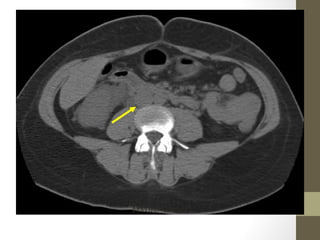

Psoas Abscess

Retroperitoneal Abscess

• 38.

• 39.